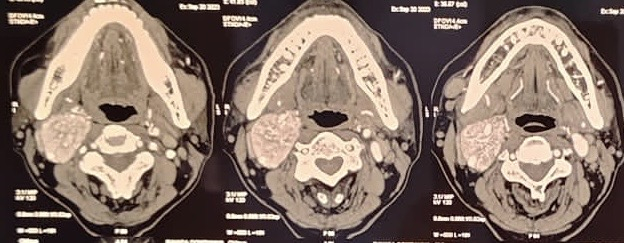

A 66-year-old female presented with a right-sided neck swelling of 3 months’ duration, accompanied by intermittent dull headaches and episodic sweating. Physical examination revealed a 7×4 cm firm, expansile mass in the right carotid triangle, mobile horizontally, with palpable pulsations and intact cranial nerve function. Imaging with CT angiography, contrast-enhanced MRI, and digital subtraction angiography demonstrated a highly vascular, enhancing mass at the carotid bifurcation causing splaying of the internal and external carotid arteries—characteristic of a carotid body tumor. Additionally, enlarged right cervical lymph nodes suggestive of paragangliomas were noted.